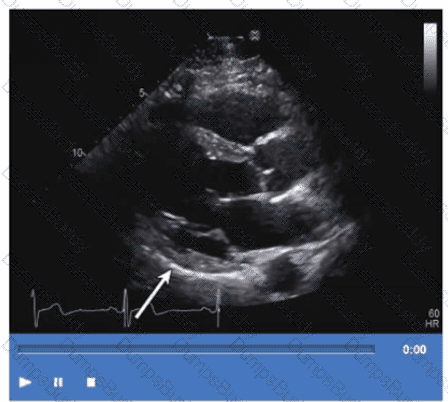

Which next step is appropriate after obtaining the Doppler signal in this image?